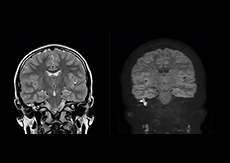

Excellent cholesteatoma imaging with Diffusion TSE

“Imaging cholesteatoma, benign tumors of the middle ear, has been a huge challenge,” says Dr. Heggelman. “We used to do CT, but then we were unsure if we were looking at an inflammation or a cholesteatoma. Also determining if residual cholesteatoma exist after surgery or visualizing recurrence used to be very difficult. Adding Diffusion TSE in our MRI protocol now effectively addresses this.” “Diffusion TSE is far less sensitive to susceptibility differences than previously used EPI sequences. We appreciate the high resolution and the robustness of the sequence. The quality is so good that our confidence has increased. Also our ENT (ear, nose, throat) physicians are excited about the high resolution, the excellent lesion delineation and the sensitivity and specificity.”